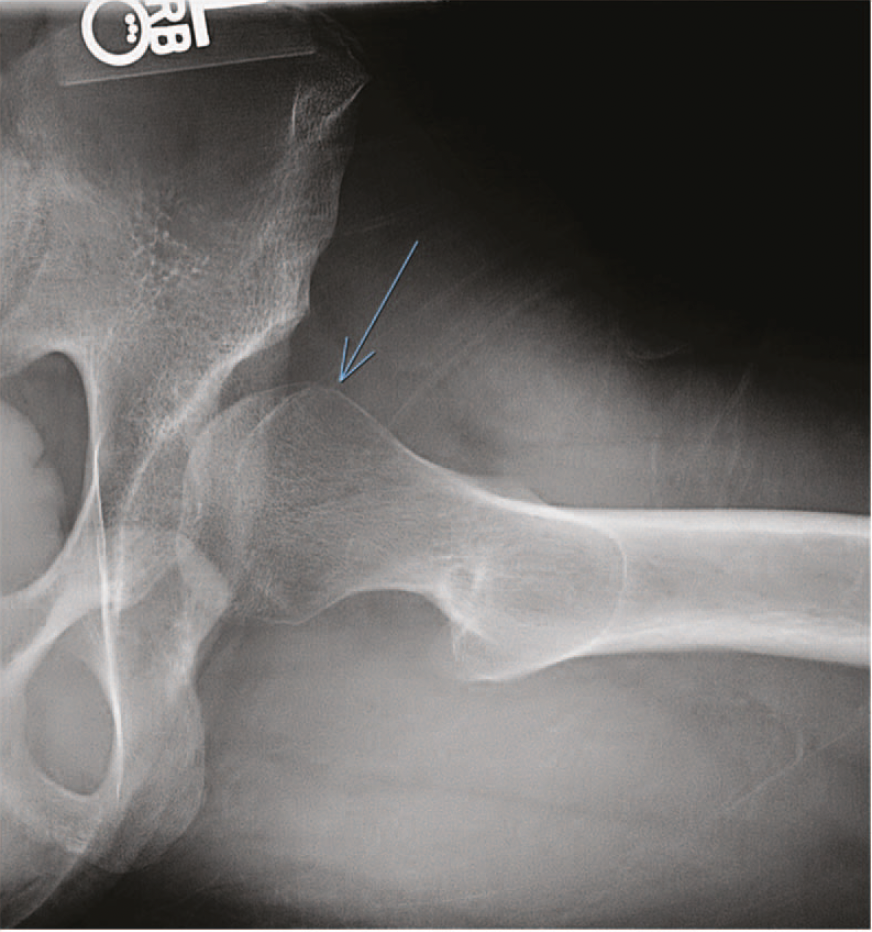

Bildgebende Verfahren: Röntgenaufnahmen helfen bei der Beurteilung knöcherner Fehlformen. Die sensitivste Methode zur Darstellung eines Labrumrisses ist die Magnetresonanz-Arthrographie (MRA). Konventionelle MRT-Untersuchungen zeigen einen Labrumriss hingegen nicht immer zuverlässig (Groh & Herrera, 2009; Su et al., 2019).